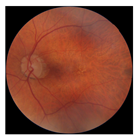

| No. | Fundus Image | Grad-CAM | Group | PRS | CNN | CNN+ML |

|---|---|---|---|---|---|---|

| 1 |  |  | Control | −2.13 | 0.63 | −0.34 |

| 2 |  |  | Control | −2.61 | 1.80 | −1.48 |

| 3 |  |  | AMD | 1.08 | 0.52 | −0.60 |

| 4 |  |  | AMD | −0.39 | −0.16 | −0.41 |